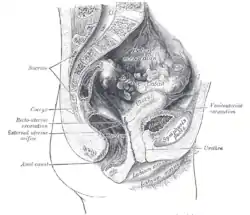

Rotational direction

Anteversion and retroversion are complementary terms describing an anatomical structure that is rotated forwards (towards the front of the body) or backwards (towards the back of the body), relative to some other position. They are particularly used to describe the curvature of the uterus.[49][50]

- Anteversion (from Latin anteversus) describes an anatomical structure being tilted further forward than normal, whether pathologically or incidentally.[49] For example, a woman's uterus typically is anteverted, tilted slightly forward. A misaligned pelvis may be anteverted, that is to say tilted forward to some relevant degree.

- Retroversion (from Latin retroversus) describes an anatomical structure tilted back away from something.[50] An example is a retroverted uterus.[50]